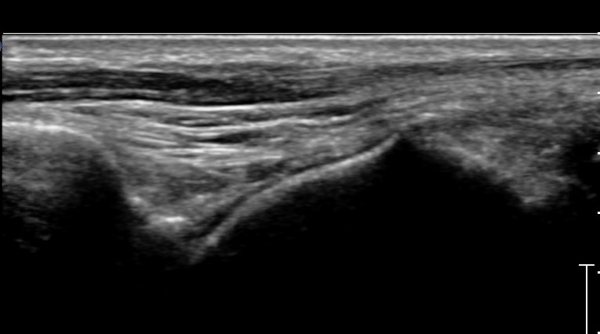

Àü°ÅºñÀδë Á¾´Ü¸é°Ë»ç»ó Àü°ÅºñÀδëÀÇ Àú¿¡ÄÚ À§Ãà°ú Á·±Ùµ¿(sinus tarsi) ¼ö¾×Àú·ù°¡

°üÂûµÈ´Ù(»çÁø 2, 3).